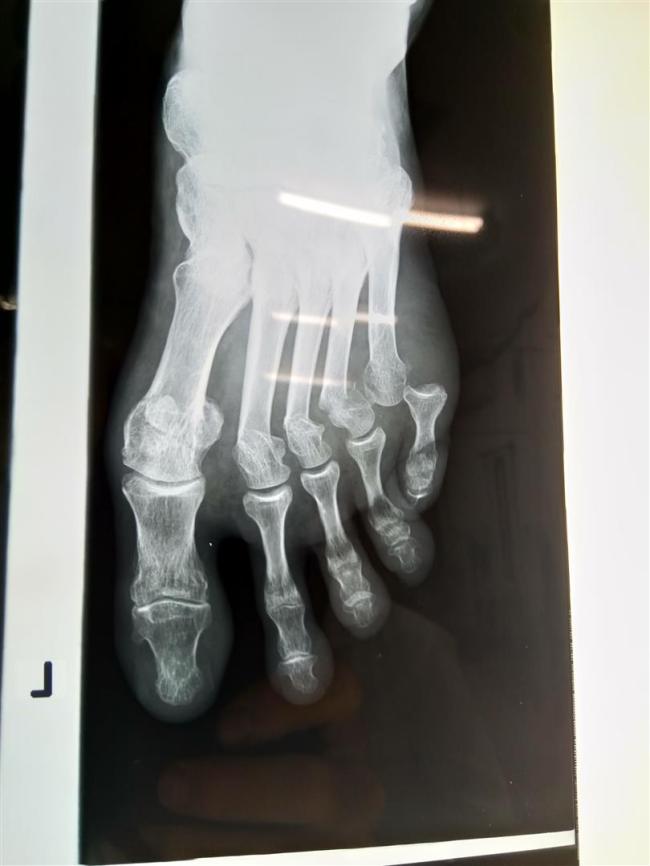

We rested up for a while but decided there was no option other than going to the hospital to get checked out. I’d hoped my foot was only bruised but the fact that several toes were pushed over to the left suggested something worse. An x-ray at the surprisingly well equipped hospital confirmed my fears. I had broken three metatarsals and dislocated my little toe. The doctor gave me a local anaesthetic and put the little toe back in place then put a plaster slab around my foot. Michael’s ribs were only bruised, fortunately. We made a right pair of old cripples, with our matching grazes and limping walk. On the way back to the guesthouse we had to stop at a pharmacy so I could buy a pair of old fashioned, wooden crutches. The worst part of all this was the damage it did to my forward plans. I’d wanted to explore the north of Laos before heading back to Thailand, where I’d leave my bike while I was back in the UK for Christmas. Those plans were blown out of the water and needed a rethink. To say I was fed up would be the understatement of 2018. It was even more galling to think that none of it would have happened if I could have been bothered to ride my own bike.

Three broken metatarsals and a dislocated toe. (The white bars are reflected lights, not pins.)